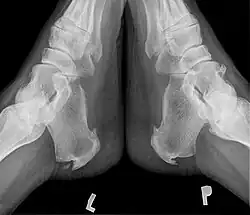

W czasie badania palpacyjnego stwierdza się bolesność uciskową powyżej wyrostka przyśrodkowego guza piętowego. Czasami występuje również ból sąsiadującego pasma rozcięgna podeszwowego. Potwierdzenie rozpoznania uzyskuje się dzięki wykonaniu RTG stóp, które wykazuje ostrą dziobiastą narośl kostną biegnącą od guza pięty ku przodowi, o różnym stopniu nasilenia[2].